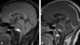

Cystic craniopharyngioma

A craniopharyngioma is a rare type of brain tumor derived from pituitary gland embryonic tissue that occurs most commonly in children, but also affects adults. It may present at any age, even in the prenatal and neonatal periods, but peak incidence rates are childhood-onset at 5–14 years and adult-onset at 50–74 years. [Source: Wikipedia ]